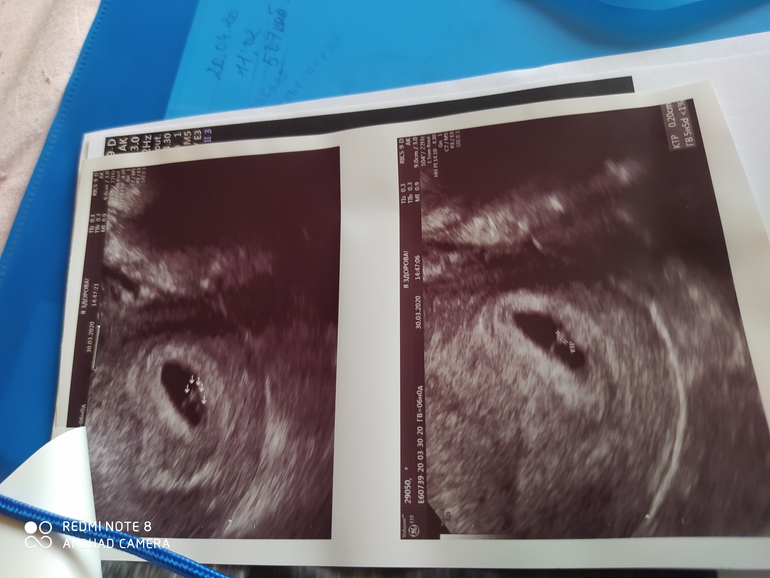

Привет!Сегодня эмбрион,сб+ все ок.ПЯ 15,4

Там намеряли 17 и пустое 👌

Ого...понятно,видимо узи только у ре надо делать.А растёт как положено,по 1 мм в день?